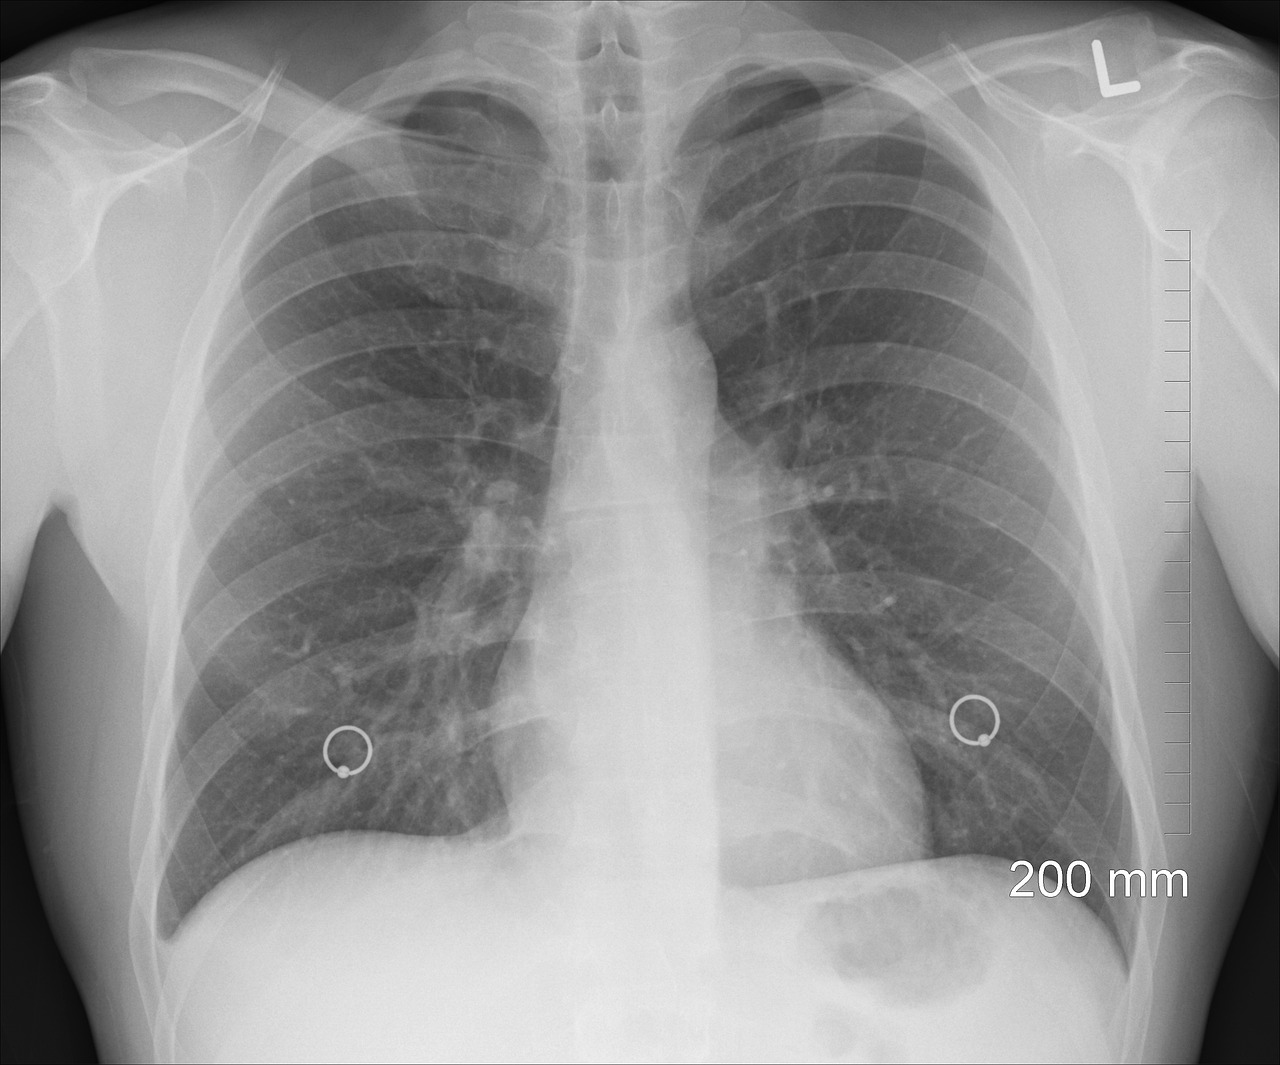

Diagnóstico do Pneumotórax: Como Identificar o Ar no Peito

Quando você chega ao hospital com dor no peito e falta de ar, a primeira coisa que o médico vai querer é uma imagem. O método mais comum e eficaz para diagnosticar o pneumotórax é o raio-X de tórax. Ele mostra claramente se há ar no espaço pleural e o quanto o pulmão foi afetado.

Em alguns casos, quando o raio-X não é conclusivo ou para avaliar melhor a extensão do problema, pode ser solicitado um exame de tomografia computadorizada (TC) de tórax. Esse exame oferece imagens mais detalhadas das estruturas pulmonares.

O médico também fará uma avaliação clínica detalhada, ouvindo seus pulmões com o estetoscópio e perguntando sobre seus sintomas e histórico de saúde. A combinação desses elementos leva ao diagnóstico preciso.